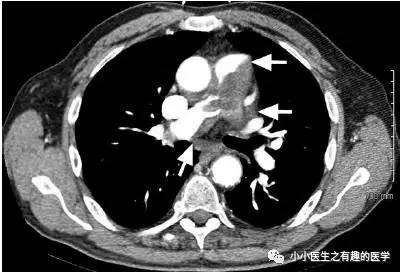

文献8:美国德克萨斯州心脏研究所。

77岁男性,外院转入。

A 77-year-old man was transferred from another hospital for treatment of a saddle PA embolus.

外院已经给予溶栓、抗凝。

He had been treated with thrombolytic and anticoagulant agents without clinical improvement.

然而,这个血栓怎么看着乱七八糟的?这是一个不正经的血栓。怎么办?牛叉的医院就喜欢简单、粗暴。

we incised the main PA and inspected the mass.切开肺动脉见肿块。

肺动脉病理:高分化肉瘤。

The histopathologic report showed a high-grade sarcoma

with focal myogenic and chondrogenic differentiation.